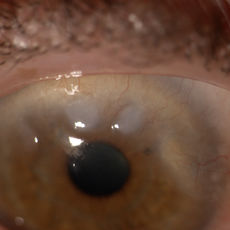

Cataratta bianca

IOL in camera anteriore